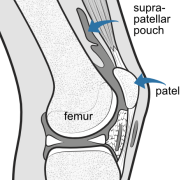

This illustration shows the knee cut through the middle. The large cavity (dark grey) extends above (suprapatellar pouch), behind and below the patella. A small suprapatellar plica is present but it does not form a complete septum so the whole cavity is open to the joint..